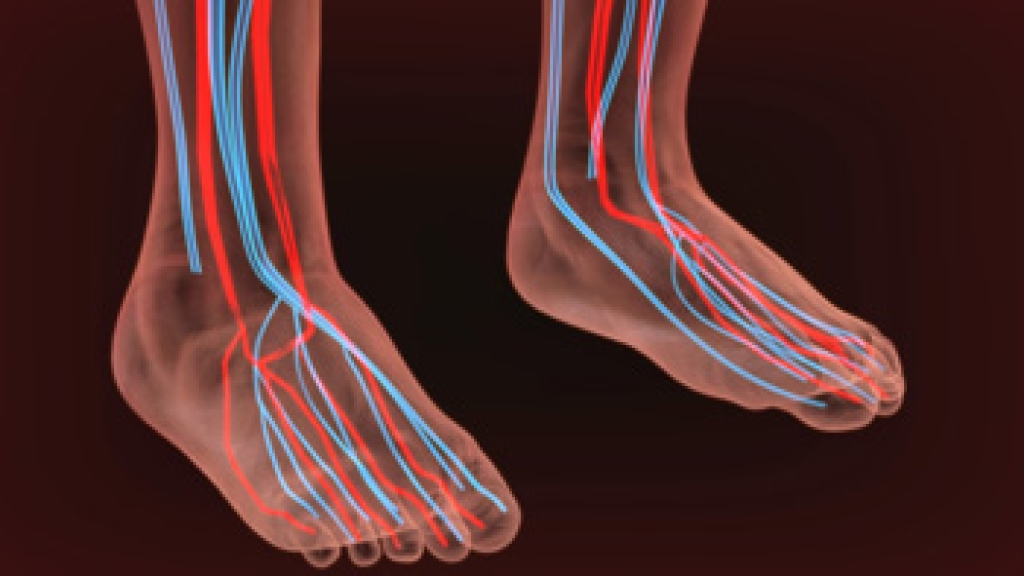

Circulation Problems and the Feet

Circulation problems in the feet occur when blood flow to the feet, toes, or ankles is restricted due to narrowed arteries. Poor circulation is often the result of atherosclerosis, where plaque builds up in the blood vessels. A result of poor circulation is peripheral arterial disease, or PAD. Patients with PAD may experience symptoms like numbness, tingling, burning sensations, or cramping in the feet or lower legs during activity. Additional signs include cool, pale skin, hair loss on the feet, slow-healing sores, and a diminished pulse. People with diabetes, high cholesterol, high blood pressure, or a history of smoking are at increased risk of developing PAD. A podiatrist can assess your circulation issues through non-invasive tests, such as the ankle-brachial index, or ABI, or a Doppler ultrasound to determine blood flow and identify any blockages. Timely diagnosis and treatment by a podiatrist can help reduce symptoms and prevent complications, like non-healing foot wounds or infections. If you have circulation problems in the feet, it is suggested that you schedule an appointment with a podiatrist for an exam and treatment.

Poor blood circulation in the feet and legs is can be caused by peripheral artery disease (PAD), which is the result of a buildup of plaque in the arteries.

Plaque buildup or atherosclerosis results from excess calcium and cholesterol in the bloodstream. This can restrict the amount of blood which can flow through the arteries. Poor blood circulation in the feet and legs are sometimes caused by inflammation in the blood vessels, known as vasculitis.

Lack of oxygen and oxygen from poor blood circulation restricts muscle growth and development. It can also cause:

Those who have diabetes or smoke are at greatest risk for poor circulation, as are those who are over 50. If you have poor circulation in the feet and legs it may be caused by PAD and is important to make changes to your lifestyle in order to reduce risk of getting a heart attack or stroke. Exercise and maintaining a healthy lifestyle will dramatically improve conditions.